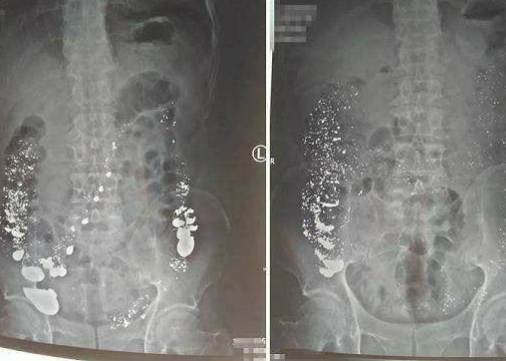

1月1日,西安市中心医院职业病中毒科救治一名喝大量水银的患者,经救治大量水银已排出,目前肠道内仅存有少量散在水银,患者已脱离生命危险,后续还需要进行复查。

白银网(http://www.zhongguobaiyin.com/)01月11日讯,大家都知道水银是有剧毒的,一般都不会碰,不过有人因跟他人发生矛盾竟然冲动之下喝下水银,据报道称,1月1日,西安市中心医院职业病中毒科救治一名喝大量水银的患者,经救治大量水银已排出,目前肠道内仅存有少量散在水银,患者已脱离生命危险,后续还需要进行复查。

据介绍,事发当天,喝水银患者是年近6旬的老人,他当时跟他人发生矛盾一气之下喝了4斤水银,由于喝水银量过大曾被多家医院拒绝收治,幸亏西安市中心医院职业病中毒科医生及时收治使得患者转危为安。

据了解,接诊医生进行检查后发现大量的金属异物影显在患者的胃部及肠壁,于是开始使用洗胃催吐等方法,但效果不明显,随后决定使用物理疗法和药物排毒结合的办法,每天让患者吃芹菜和韭菜促排便,通过一系列治疗患者腹胀症状也逐渐减轻,患者从发病至今无消化道穿孔迹象,目前,患者已脱离生命危险。